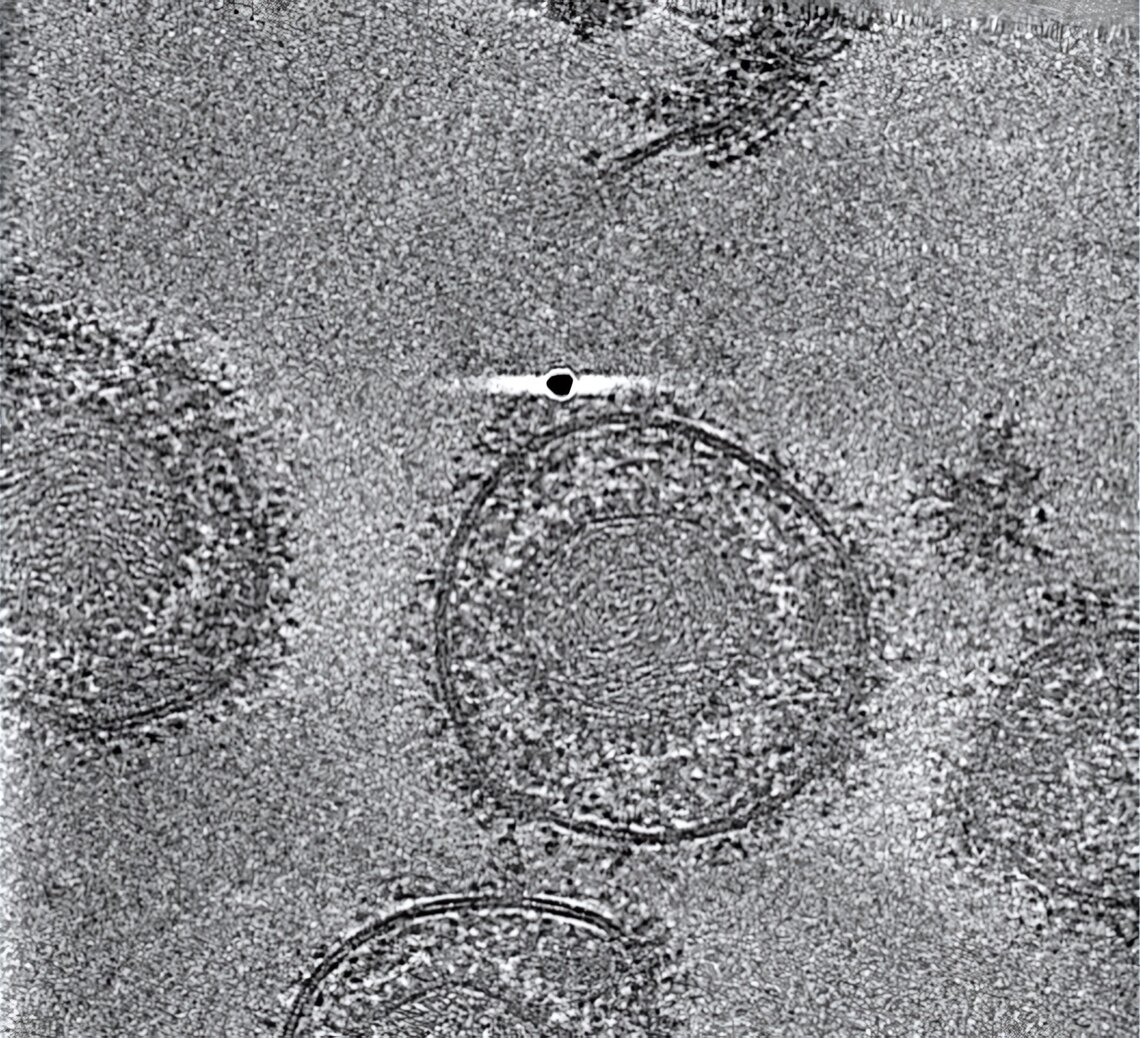

Forschende des Leibniz-Instituts für Virologie (LIV), der Universität Hamburg (UHH), und des Universitätsklinikums Hamburg-Eppendorf (UKE) am Centre for Structural Systems Biology (CSSB) in Hamburg sowie des Göttinger Max-Planck-Instituts (MPI) für Multidisziplinäre Naturwissenschaften ist es jedoch gelungen, den gB-Komplex in seiner bisher nicht zugänglichen fusionsbereiten Form zu stabilisieren. Sie konnten dessen hochaufgelöste Struktur mittels Kryo-Elektronenmikroskopie, Bildanalyse und Struktur-Modellierung bestimmen. Dabei haben die Technologieplattformen für ausgebaute Lichtmikroskopie und Kryo-Elektronenmikroskopie (Kryo-EM) am CSSB geholfen.